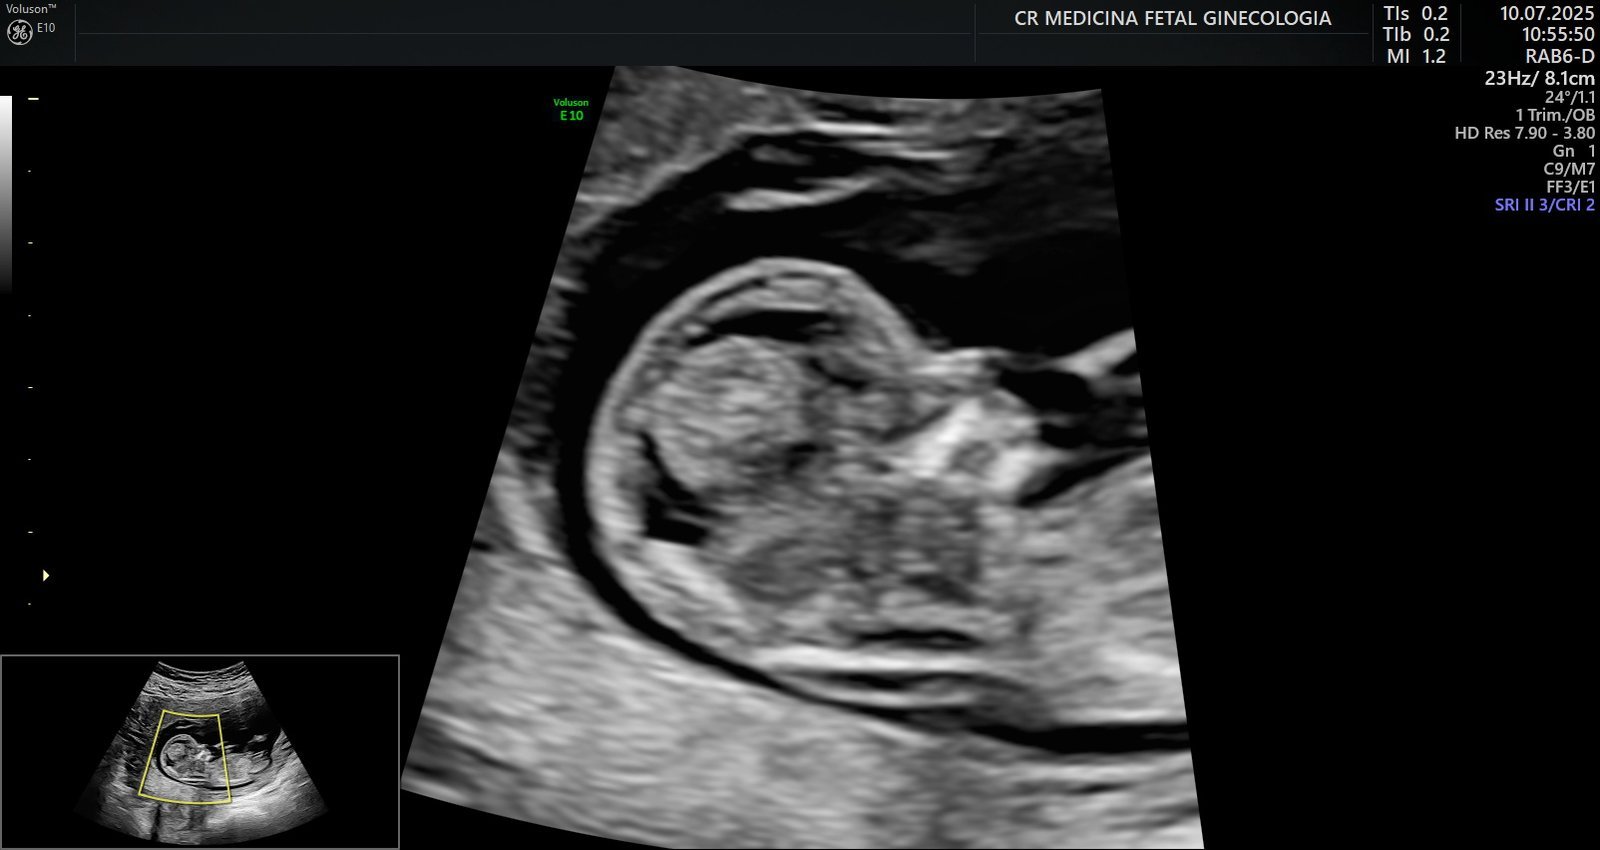

Ultrassonografia obstétrica morfológica do primeiro trimestre: Exame detalhado realizado entre a 11º – 13º semana, avalia a formação inicial do bebê e identifica possíveis riscos genéticos ou malformações precoces e chances maternas de desenvolver pré-eclâmpsia

Avaliações embrionárias e fetais completas: Análises aprofundadas desde os estágios iniciais da gestação, garantindo que cada fase seja acompanhada com precisão.